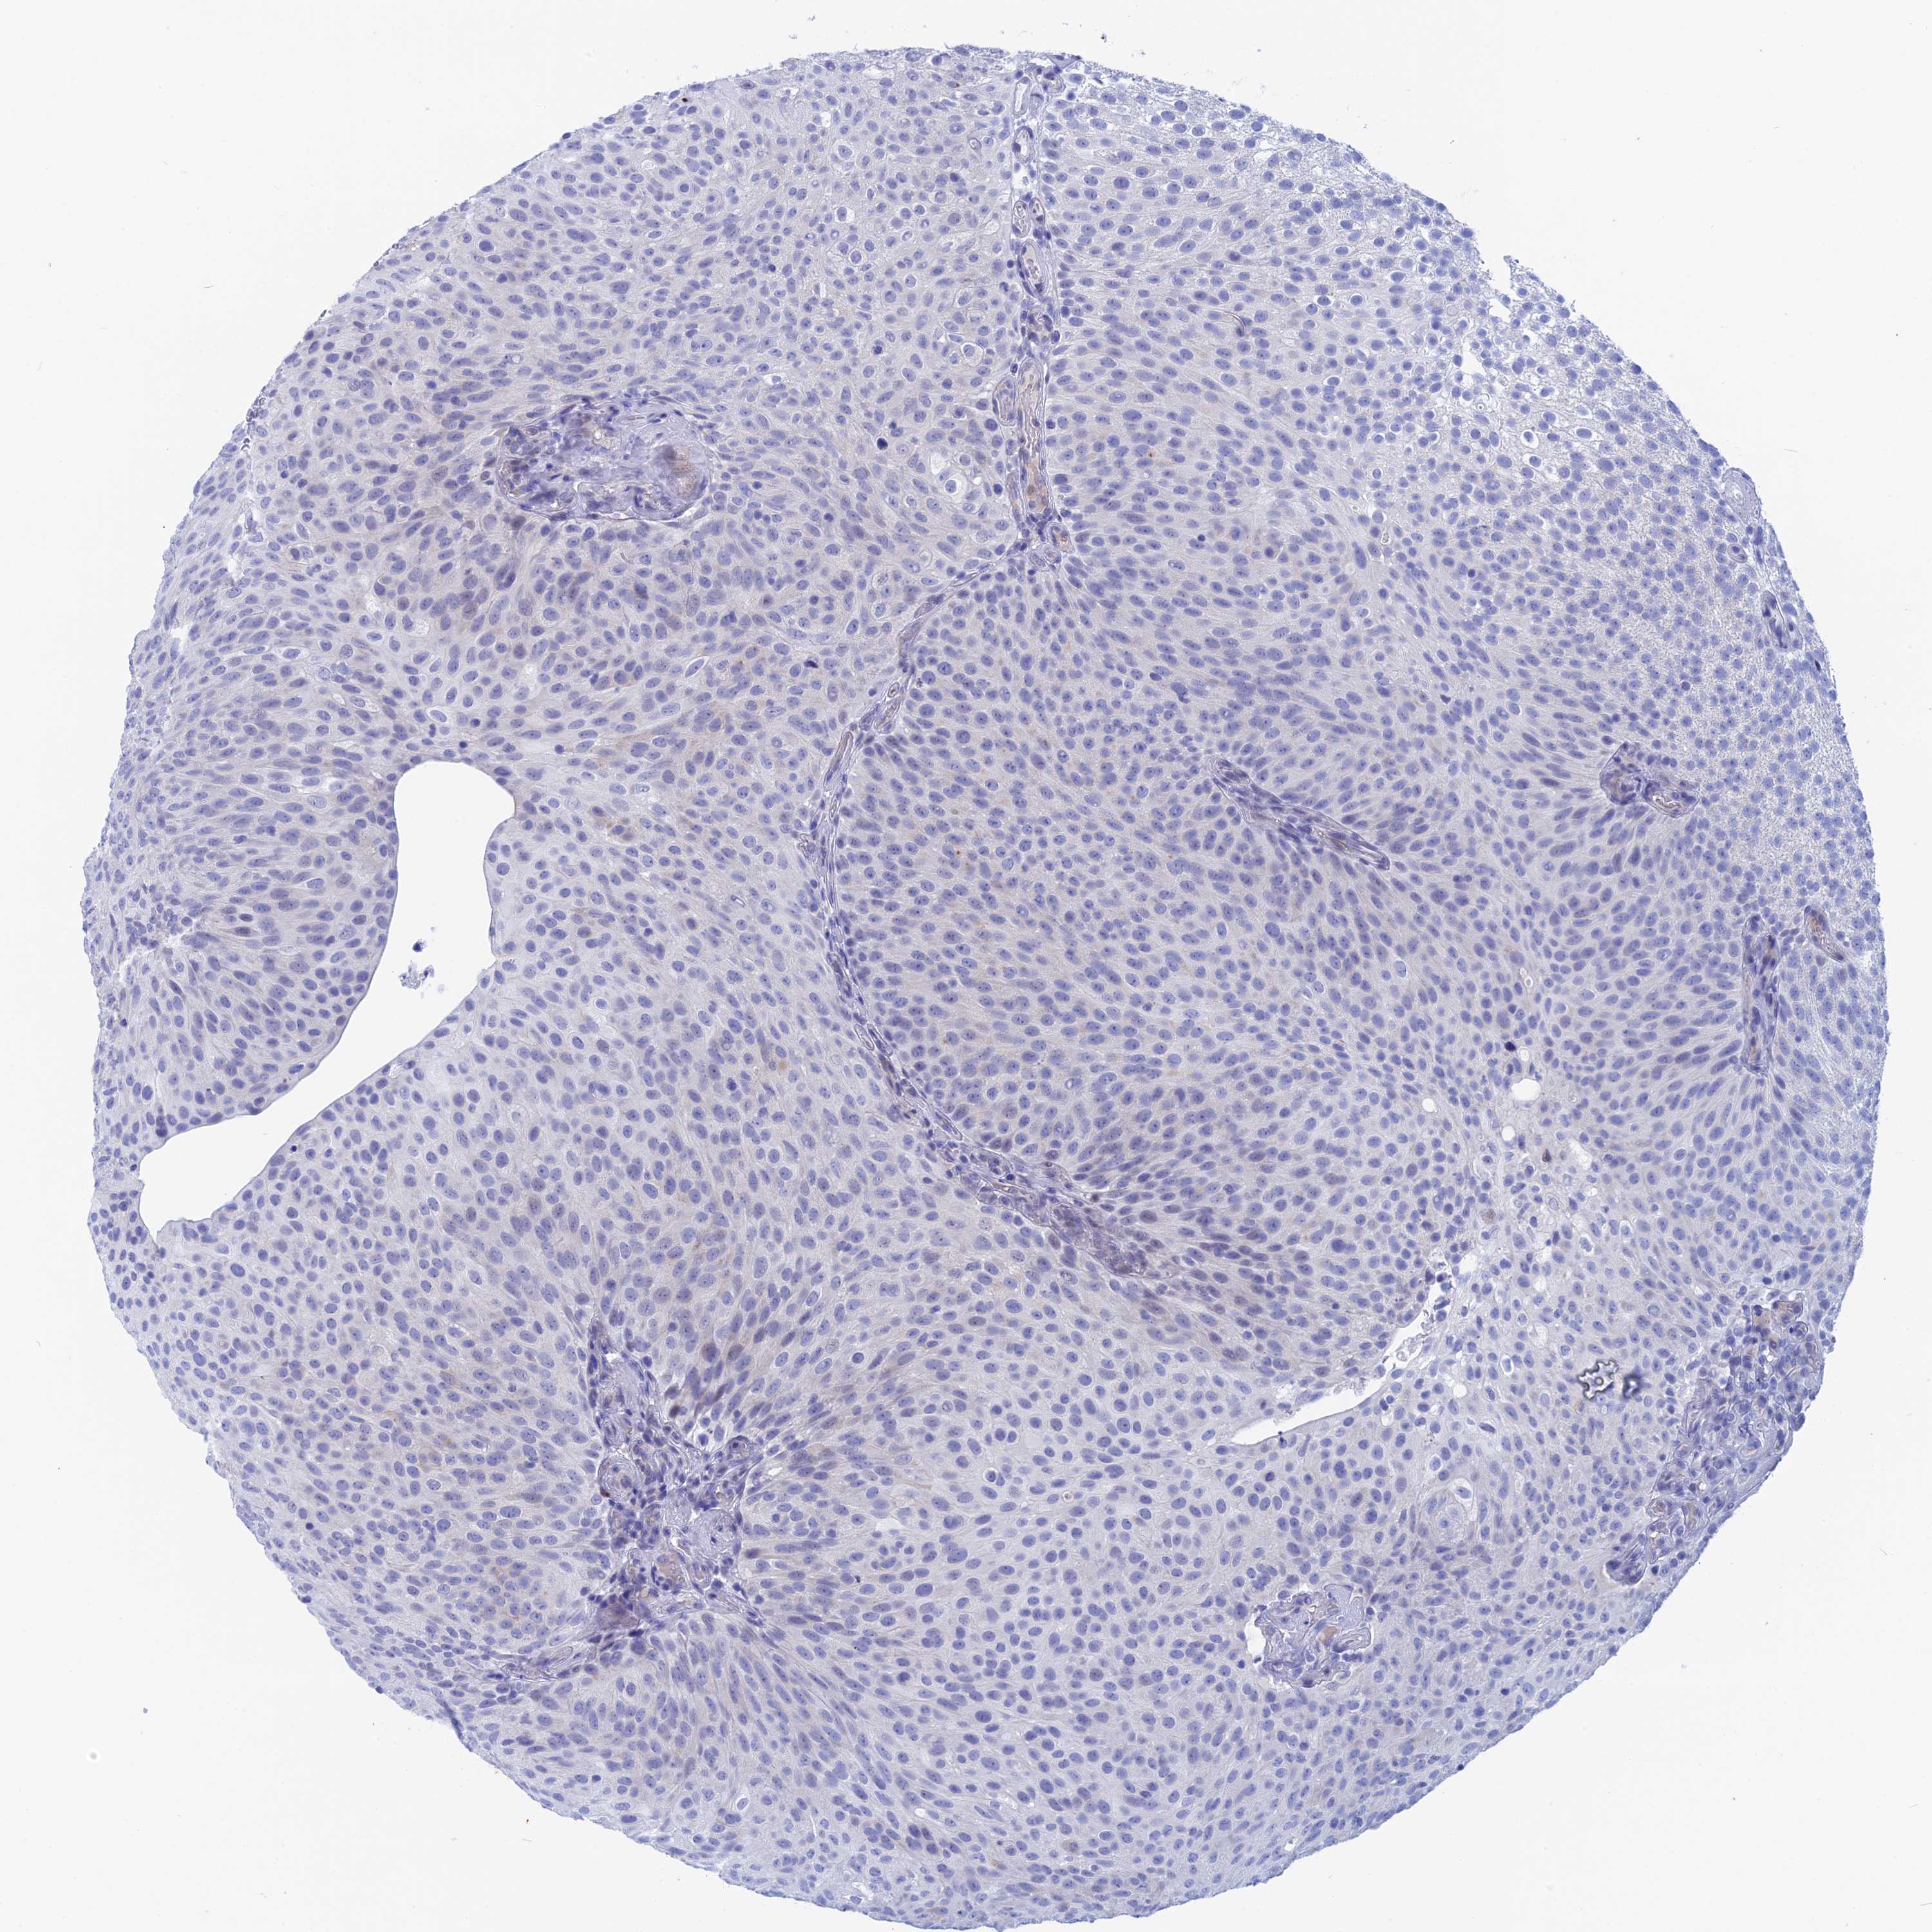

UROTHELIAL CANCER - Protein expressioni

A mouse-over function shows sample information and annotation data. Click on an image to view it in a full screen mode. Samples can be filtered based on level of antibody staining by selecting one or several of the following categories: high, medium, low and not detected. The assay and annotation is described here.

Antibody stainingi

Antibody staining in the annotated cell types in the current human tissue is reported as not detected, low, medium, or high, based on conventional immunohistochemistry profiling in selected tissues. This score is based on the combination of the staining intensity and fraction of stained cells.

Each image is clickable and will lead to virtual microscopy that enables deeper exploration of all samples and also displays staining intensity scores, fraction scores and subcellular localization as well as patient and tissue information for each sample.

Antibody HPA042629

Antibody HPA042838

Urothelial carcinoma, High grade

Urothelial carcinoma, Low grade